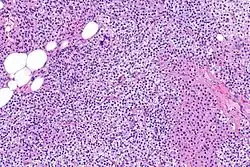

Parathyroid hyperplasia low mag.

Primary hyperplasia of the parathyroid gland, results from both hypocalcaemia and increased phosphate levels by decreasing expression of calcium sensing receptors and vitamin D receptors at the parathyroid gland.[8][4] These decreases in receptor expression lead to hyperfunctioning of the parathyroid. Hyperfunction of the parathyroid gland is thought to exacerbate primary hyperplasia which evolves further to a secondary more aggressive hyperplasia. Histologically, these hyperplasic glands can be either diffuse or nodular.[24] Primary hyperplasia, usually resulting in diffuse polyclonal growth is manly related to reversible secondary hyperparathyroidism. Secondary hyperplasia of the parathyroid gland is more often a nodular, monoclonal growth that sustains secondary hyperparathyroidism and is the catalyst in the progression to tertiary hyperparathyroidism. Nodular hyperplastic glands in tertiary hyperparathyroidism are distinctly larger in both absolute size and weight up to 20-40-fold increases have been reported.[25][26][24]

Parathyroid hyperplasia medium mag.

Parathyroid glands are normally composed of chief cells, adipocytes and scattered oxyphil cells.[27][14] Chief cells are thought to be responsible for the production, storage and secretion of parathyroid hormone. These cells appear light and dark with a prominent Golgi body and endoplasmic reticulum. In electron micrographs, secretory vesicles can be seen in and around the Golgi and at the cell membrane. These cells also contain prominent cytoplasmic adipose.[27][14] Upon onset of hyperplasia these cells are described as having a nodular pattern with enlargement of protein synthesis machinery such as the endoplasmic reticulum and Golgi. Increased secretory vesicles are seen and decreased intercellular fat is characteristic.[27][24] Oxyphil cells also appear hyperplasic however, these cells are much less prominent.

Parathyroid hyperplasia high mag.